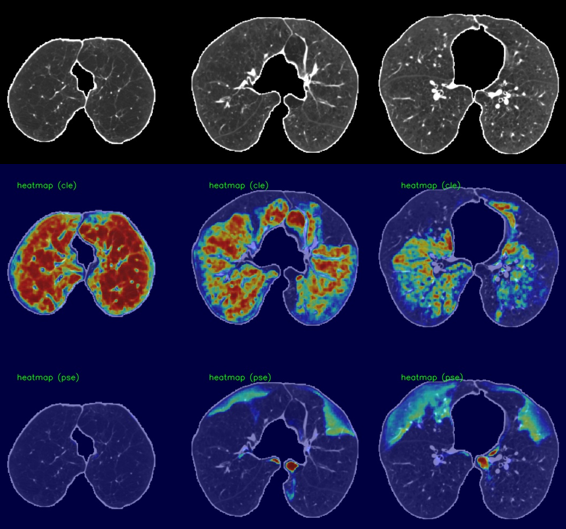

Case I: Confluence in centrilobular, Absent in Paraseptal Emphysema.

Refer to caption

(a) Class Activation Maps. Predicted Advanced for centrilobular, Substantial for Paraseptal.

(b) Regression Activation Maps. Predicted Advanced for centrilobular, Mild for Paraseptal.

Case II: Advanced in centrilobular, Substantial in Paraseptal Emphysema.

(a) Class Activation Maps. Predicted Advanced for centrilobular, Absent for Paraseptal.

Figure 3: Dense class activation maps (left) versus dense regression activation maps (right), We show two cases, and each consists of three rows. The first row shows the input image (cropped and masked by the lung segmentation), the second row illustrates the activation maps for the centrilobular emphysema, and the third row shows the activation maps for the paraseptal emphysema.

We utilized dense activation maps to visualize the features that correspond to the classification decisions. As shown in Figure 3, we present the dense class and regression activation maps on two examples of predicting centrilobular and paraseptal emphysema subtypes. Each example consists of two images, with 3×3333\times 3 tiles, where the left image displays the dense class activation maps and the right image displays the dense regression activation maps. The three columns in each image are sampled axial slices from the input CT scan. For each image, the rows represent the preprocessed input CT scan, the activation map for centrilobular emphysema, and the activation map corresponding to paraseptal emphysema.

In general, the dense class activation maps do not necessarily align with object contours, e.g., blobs of paraseptal emphysema in the second case (Fig. 3 Case II (a)). Naturally, class activation maps only reflect discriminative regions responsible for classification. By utilizing the reconstruction network to generate dense features, our network’s dense class activation maps already provide improved localization compared to the class activation maps generated by the Fleischer algorithm (which tend to be blurry blobs, as seen in their publication). The application of regression training further improves lesion localization, as can be seen in the subpleural paraseptal emphysema in the second case (Figure 3, Case II(b)) and small blobs following the secondary lobular structures in the first case (Figure 3, Case I(b)). Additionally, due to the use of the overlapping loss (Eq.2), the centrilobular and paraseptal activations do not overlap in the dense regression activation maps (Figure3, Case II(b)), unlike in the class activation maps. For instance, in the first case, both class activation maps responded to the same regions in the right lobe (Figure 3, Case I(a)). This highlights the effectiveness of our proposed method in providing improved lesion localization compared to the Fleischer algorithm.